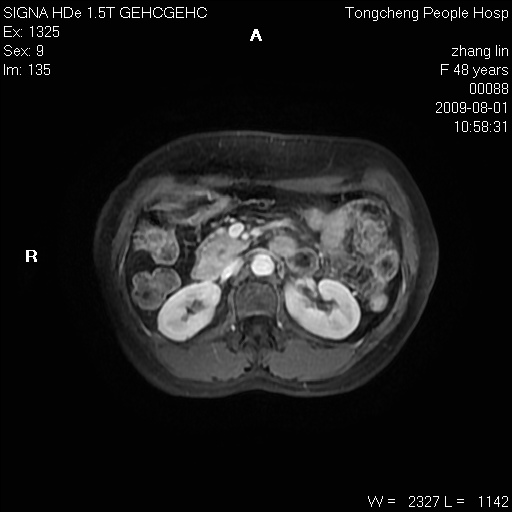

女,48岁。健康体检,彩超发现右肾占位性病变。平素健康。

临床诊断:右肾占位性病变,性质待定(囊肿?肿瘤?)。

上中腹部mr平扫+增强扫描,图像如下:

右肾上极见一类圆形病灶,t1wi呈等信号t2wi呈等高混杂信号,三期增强无强化,边界清---考虑囊肿出血。

同反相位均表现为等信号,病变无强化,考虑含蛋白的囊肿可能,弥散加权相或许有些帮助,

慢性胆囊炎